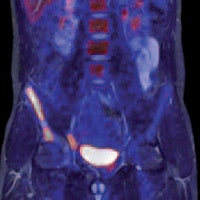

Two-station torso imaging with multitransmit. Image courtesy of Philips.